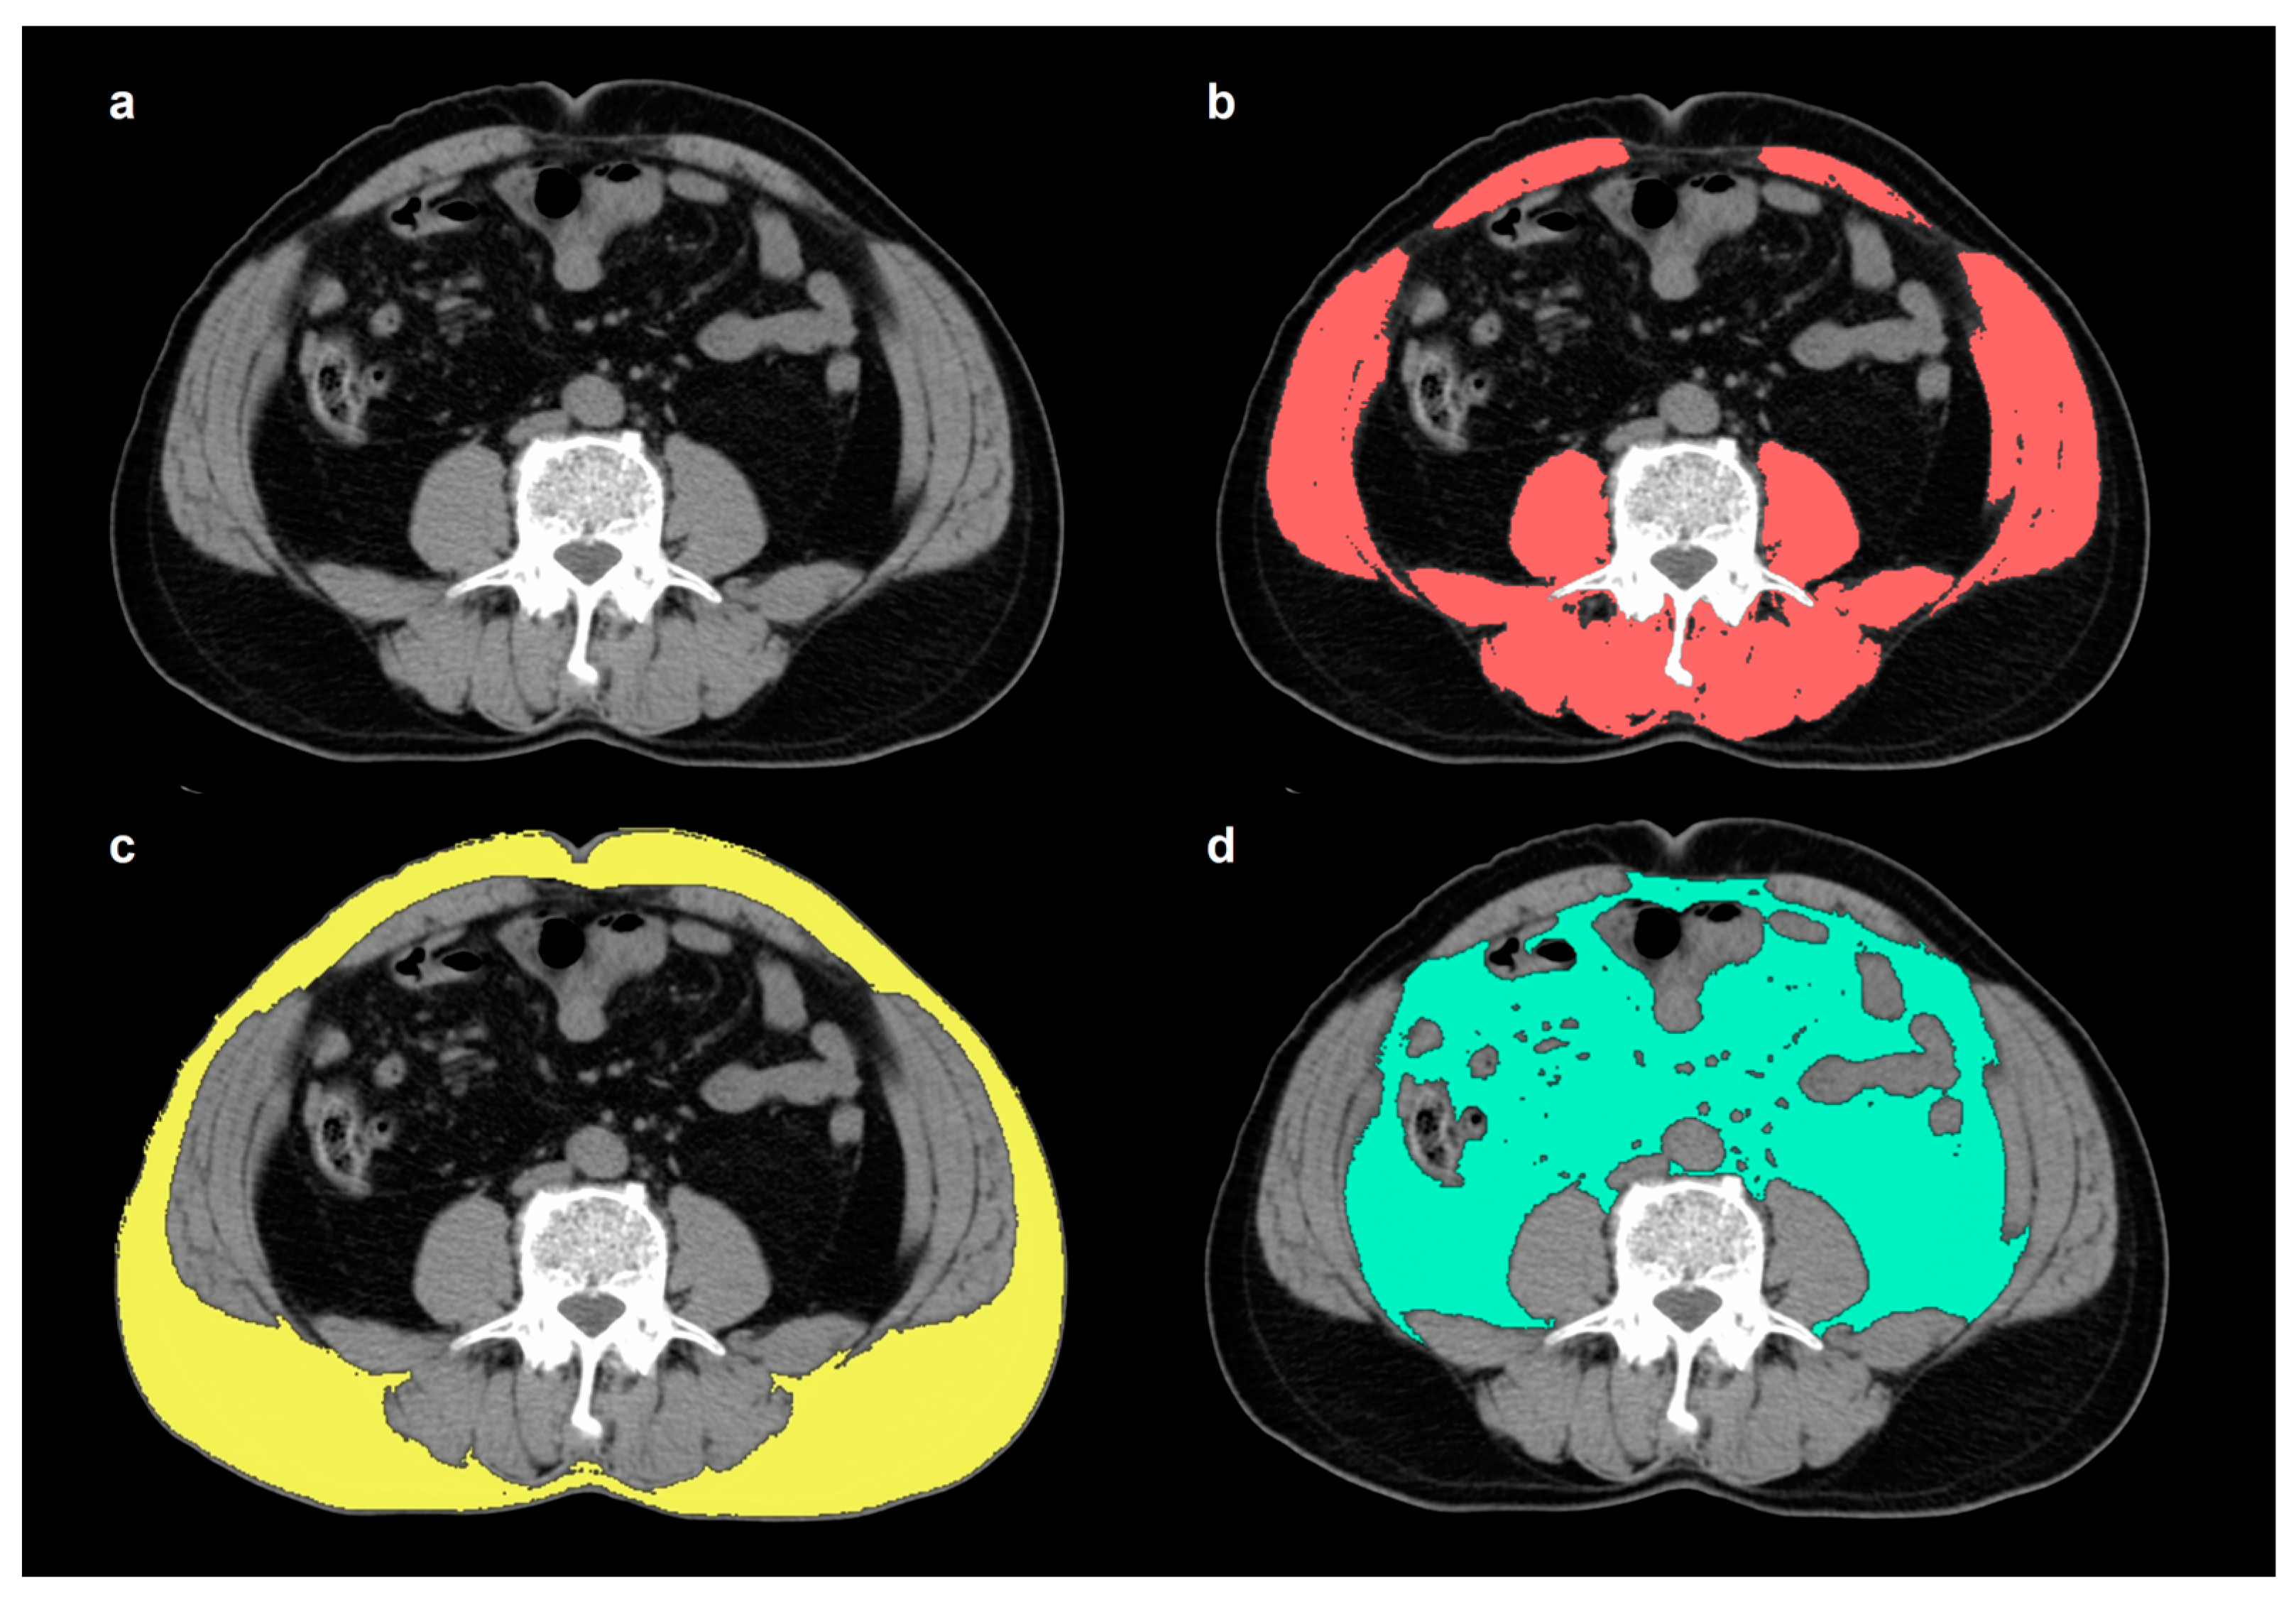

2.2. Measurement of Skeletal Muscle and Adipose Tissue